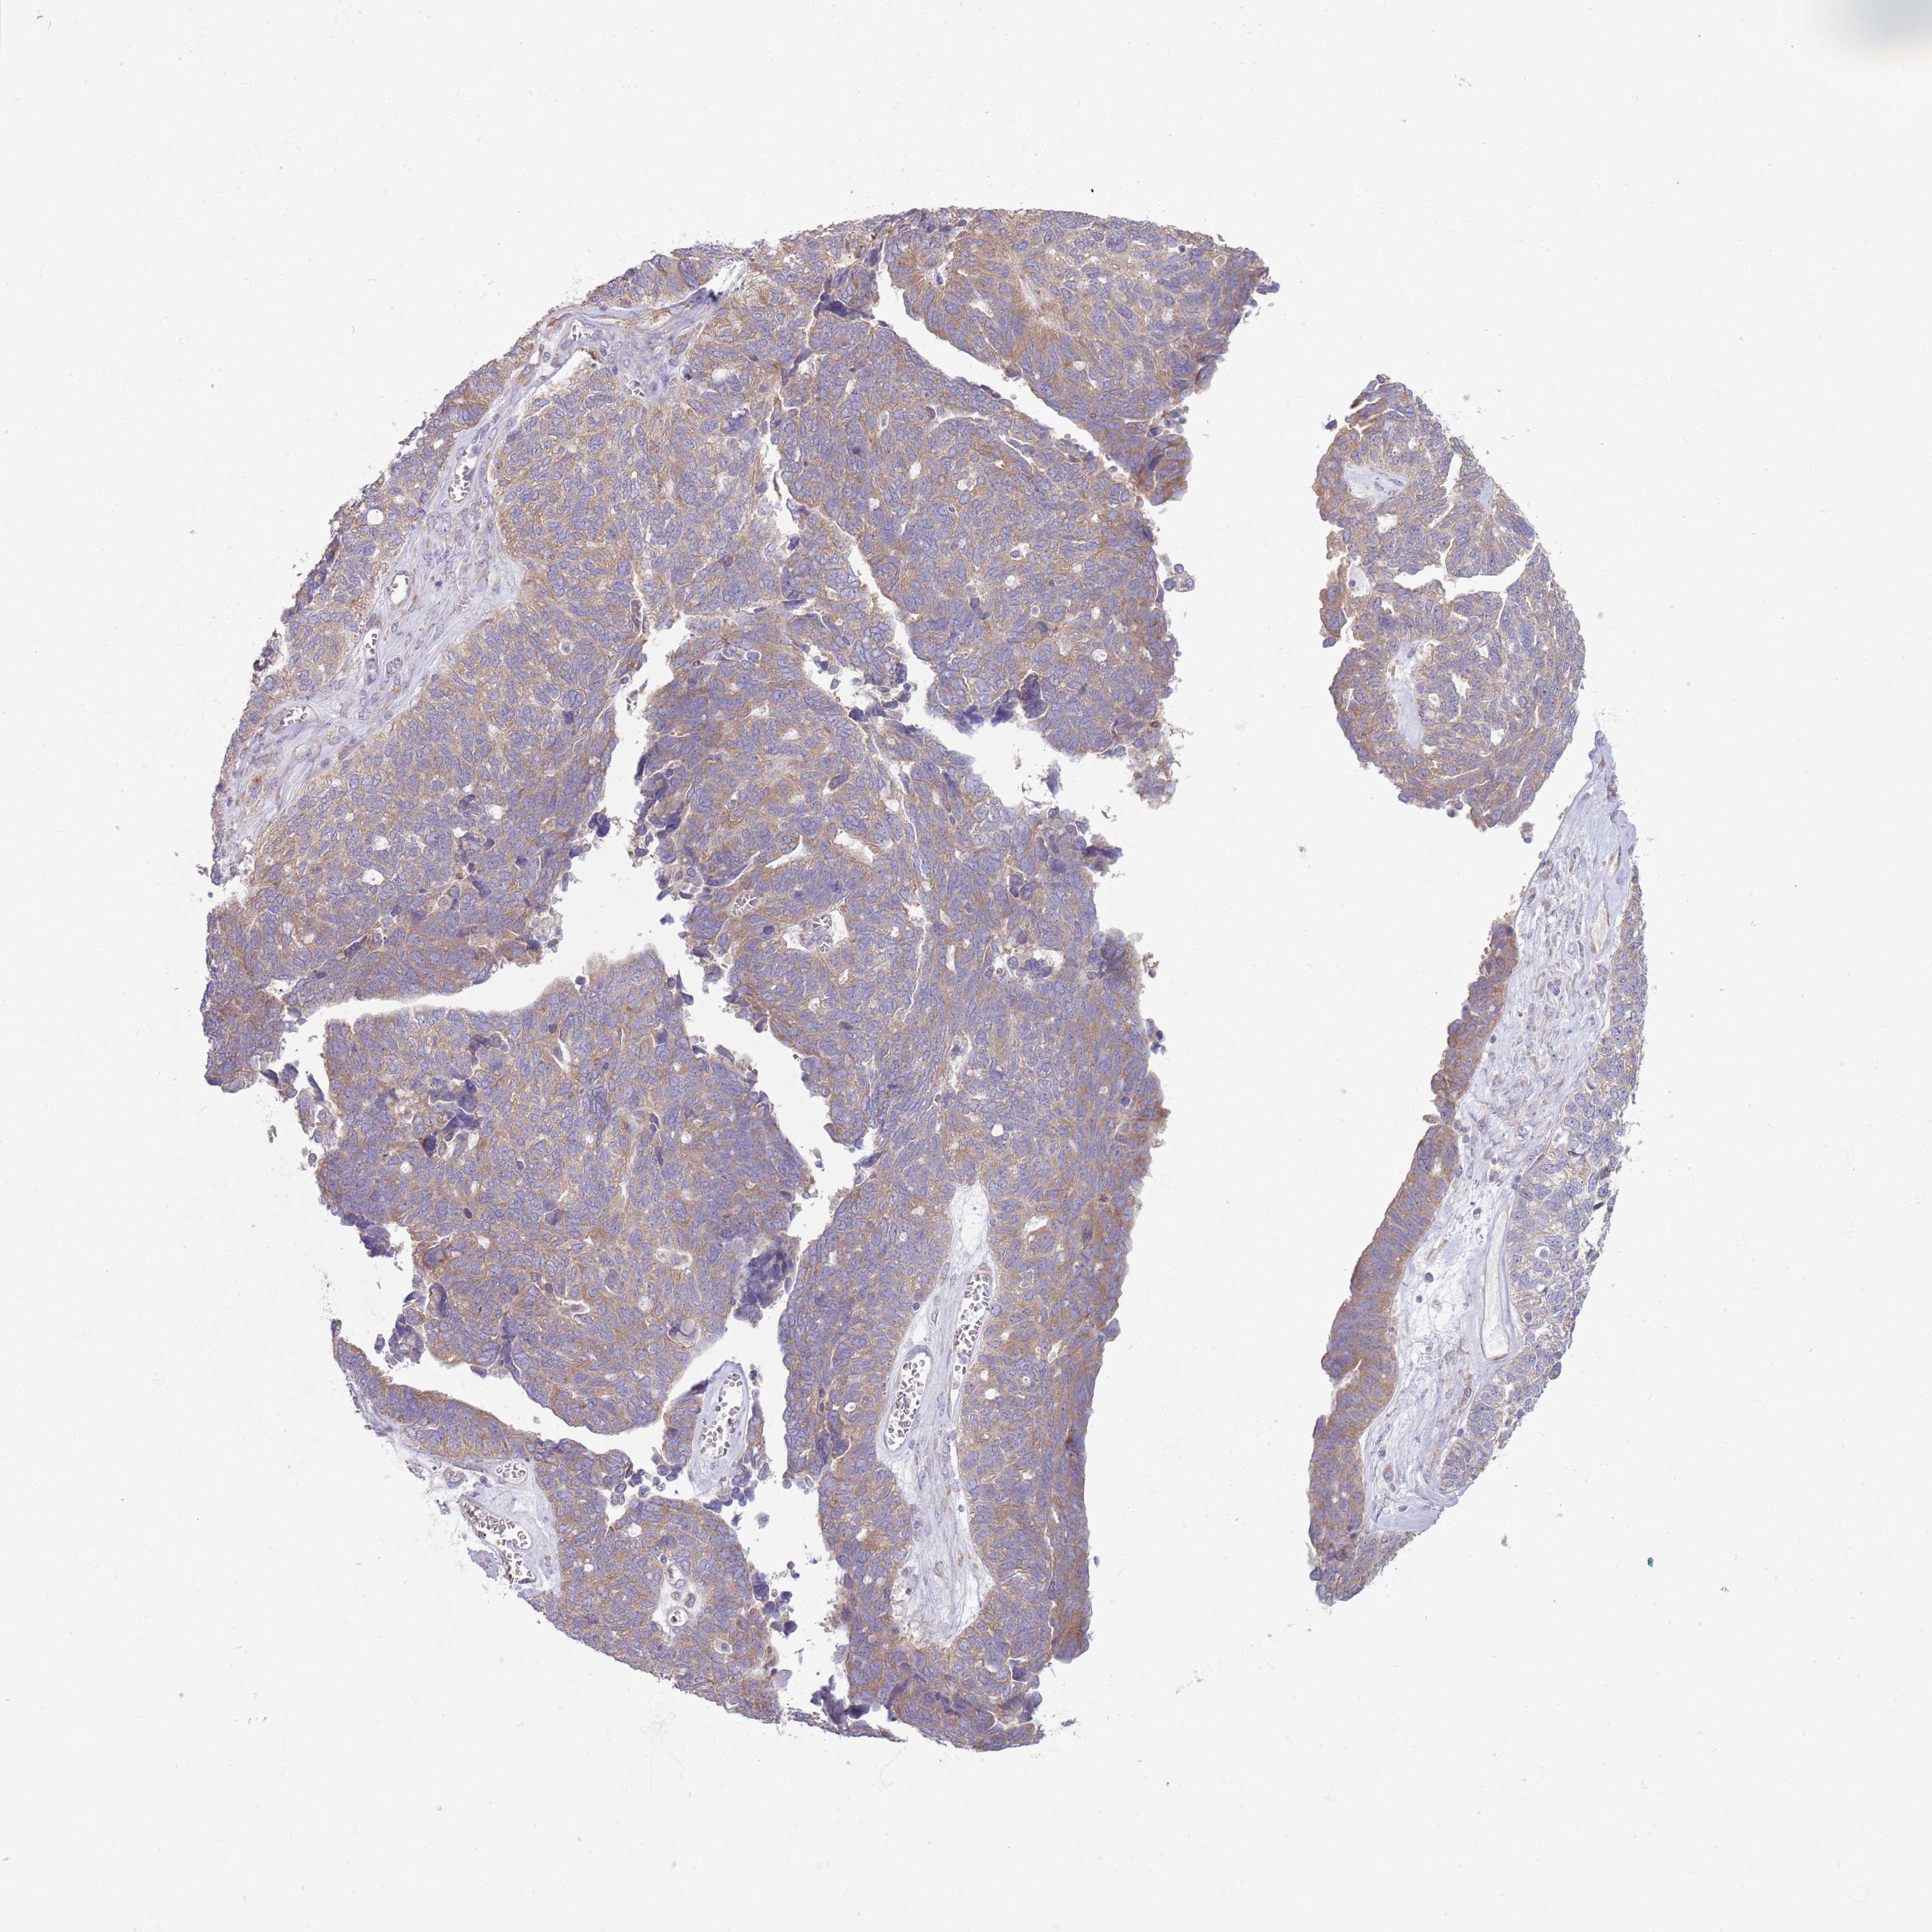

OVARIAN CANCER - Protein expressioni

A mouse-over function shows sample information and annotation data. Click on an image to view it in a full screen mode. Samples can be filtered based on level of antibody staining by selecting one or several of the following categories: high, medium, low and not detected. The assay and annotation is described here.

Note that samples used for immunohistochemistry by the Human Protein Atlas do not correspond to samples in the TCGA dataset.

Antibody stainingi

Antibody staining in the annotated cell types in the current human tissue is reported as not detected, low, medium, or high, based on conventional immunohistochemistry profiling in selected tissues. This score is based on the combination of the staining intensity and fraction of stained cells.

Each image is clickable and will lead to virtual microscopy that enables deeper exploration of all samples and also displays staining intensity scores, fraction scores and subcellular localization as well as patient and tissue information for each sample.

Antibody HPA043724

Antibody HPA046385

Cystadenocarcinoma, serous, NOS

Carcinoma, NOS

Cystadenocarcinoma, mucinous, NOS

Carcinoma, endometroid